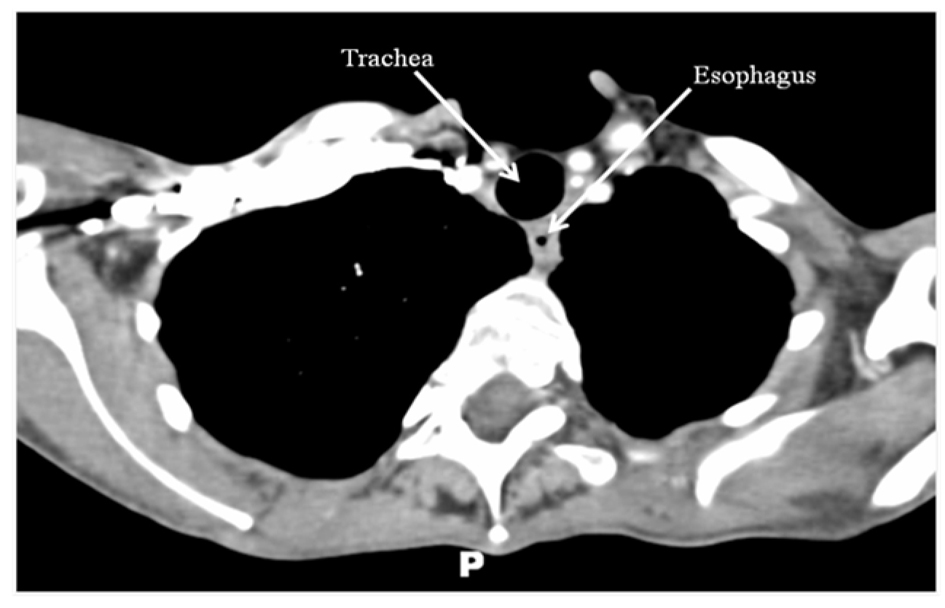

Combined chemotherapy and directed radiotherapy resulted in near complete relief of her neck symptoms after the first cycle. She completed 3 cycles of rituximab, cyclophosphamide, hydroxydaunorubicin, oncovin, and prednisone (R-CHOP) followed by 40 Gy locally directed radiotherapy. She did not require thyroidectomy or other surgical resection. Follow-up imaging 24 months after completion of therapy demonstrated complete resolution of her neck mass and no significant lymphadenopathy (Fig. 2). She remains without neck or B-type symptoms. Her anemia has resolved and her LDH is normal. She is clinically and biochemically euthyroid on levothyroxine 75 µg/day.

![]() Click for large image | Figure 2. CT scan of the neck/chest with intravenous contrast performed 24 months after treatment demonstrating complete resolution of the thyroid mass and no abnormal lymphadenopathy. |